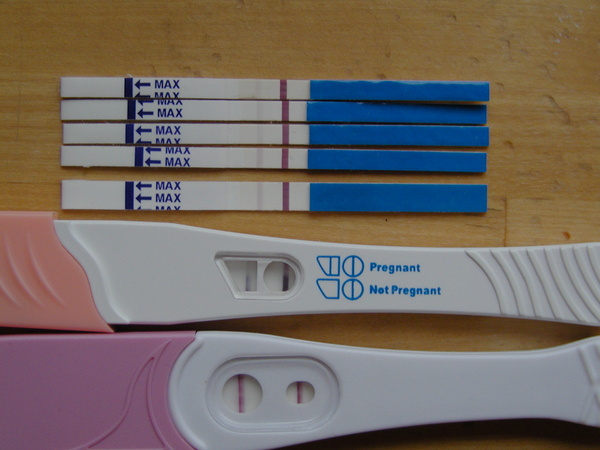

Lina! Tessék jól megválogatni azokat a teszteket!

Csak a két csíkosat fogadjuk el!